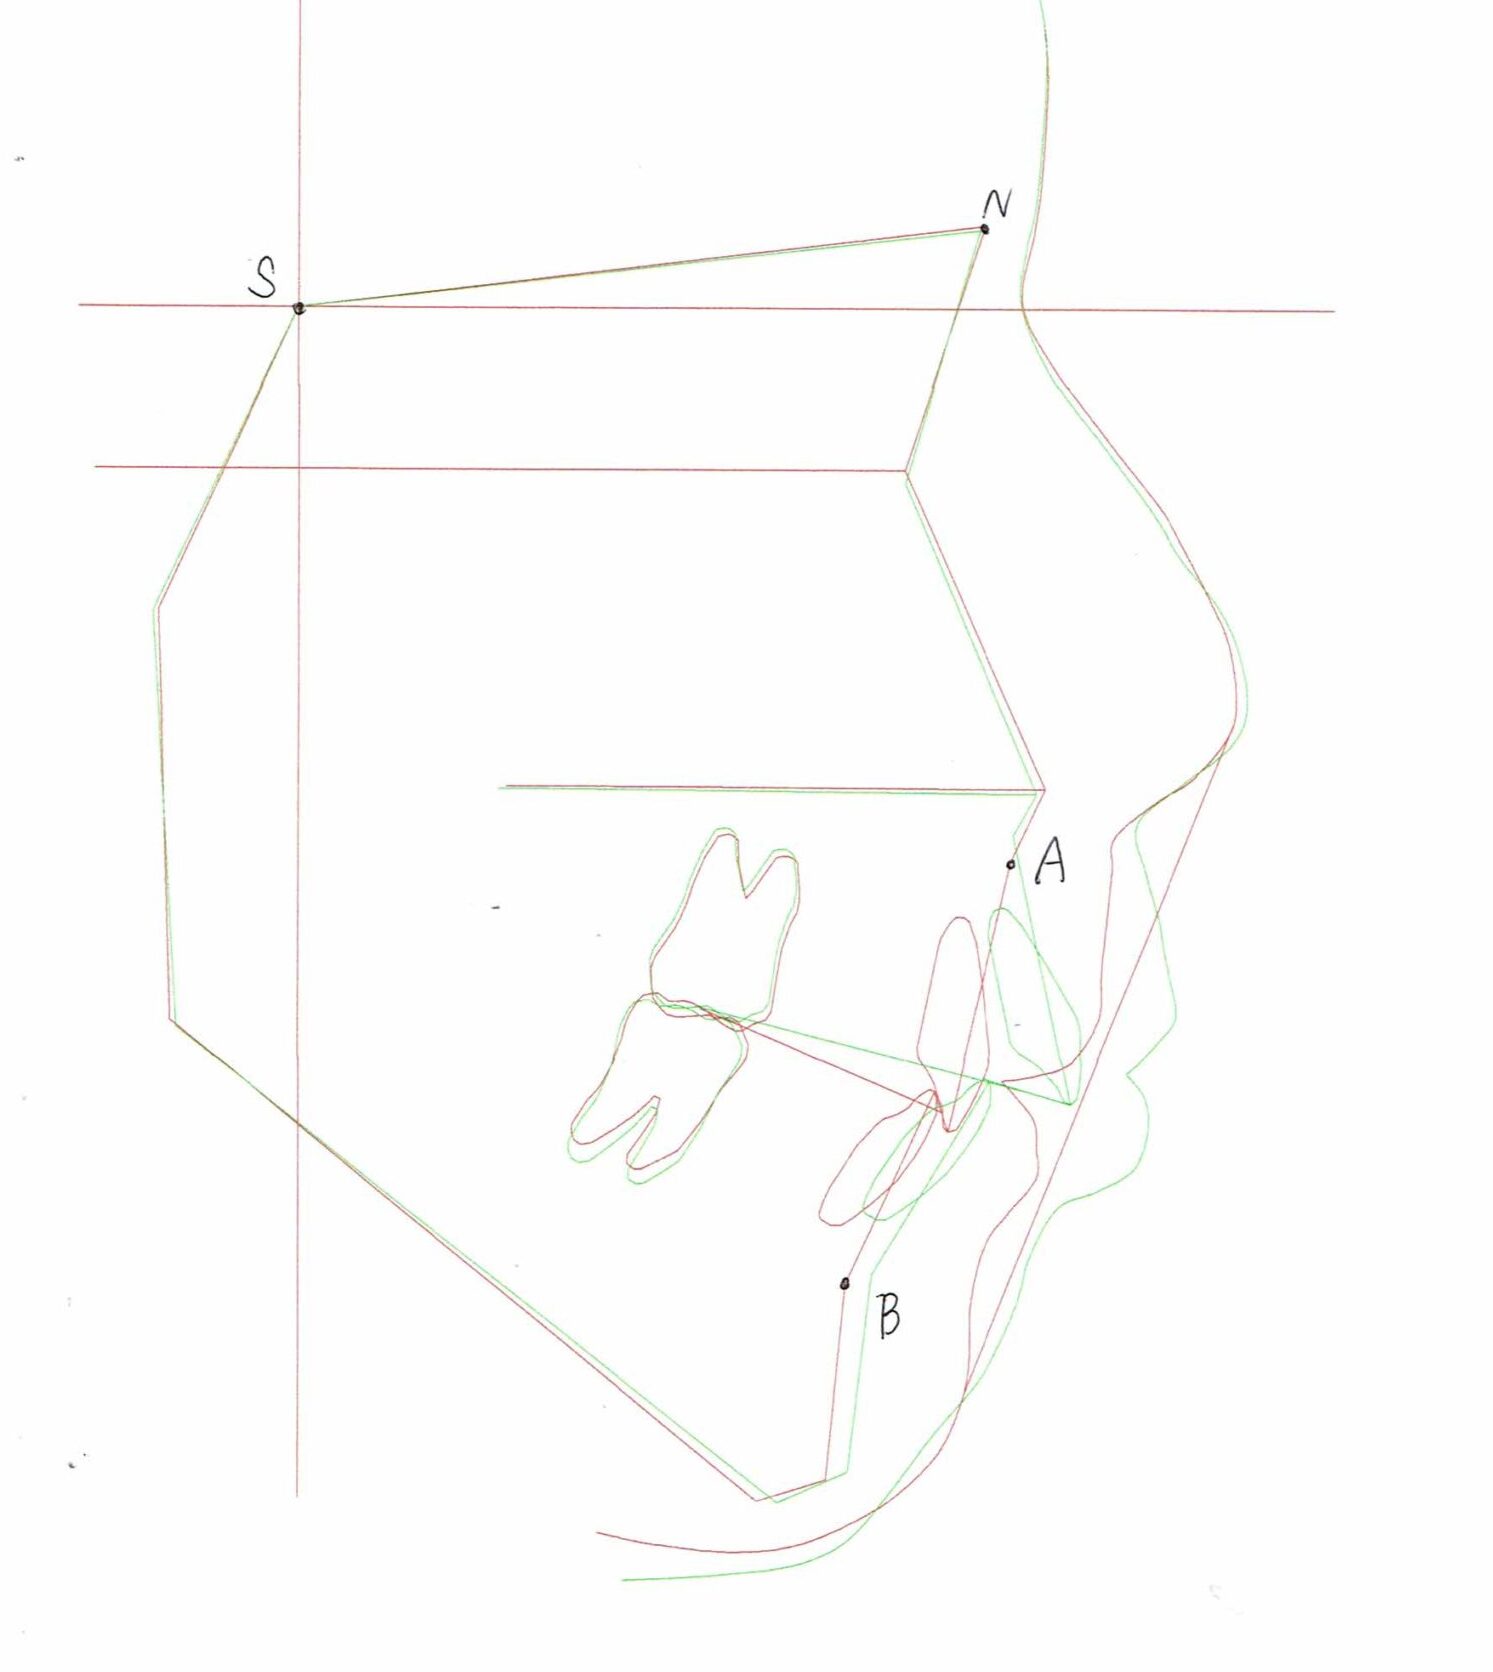

セファログラムのトレースの重ね合わせ(緑:治療前、赤:治療終了時)